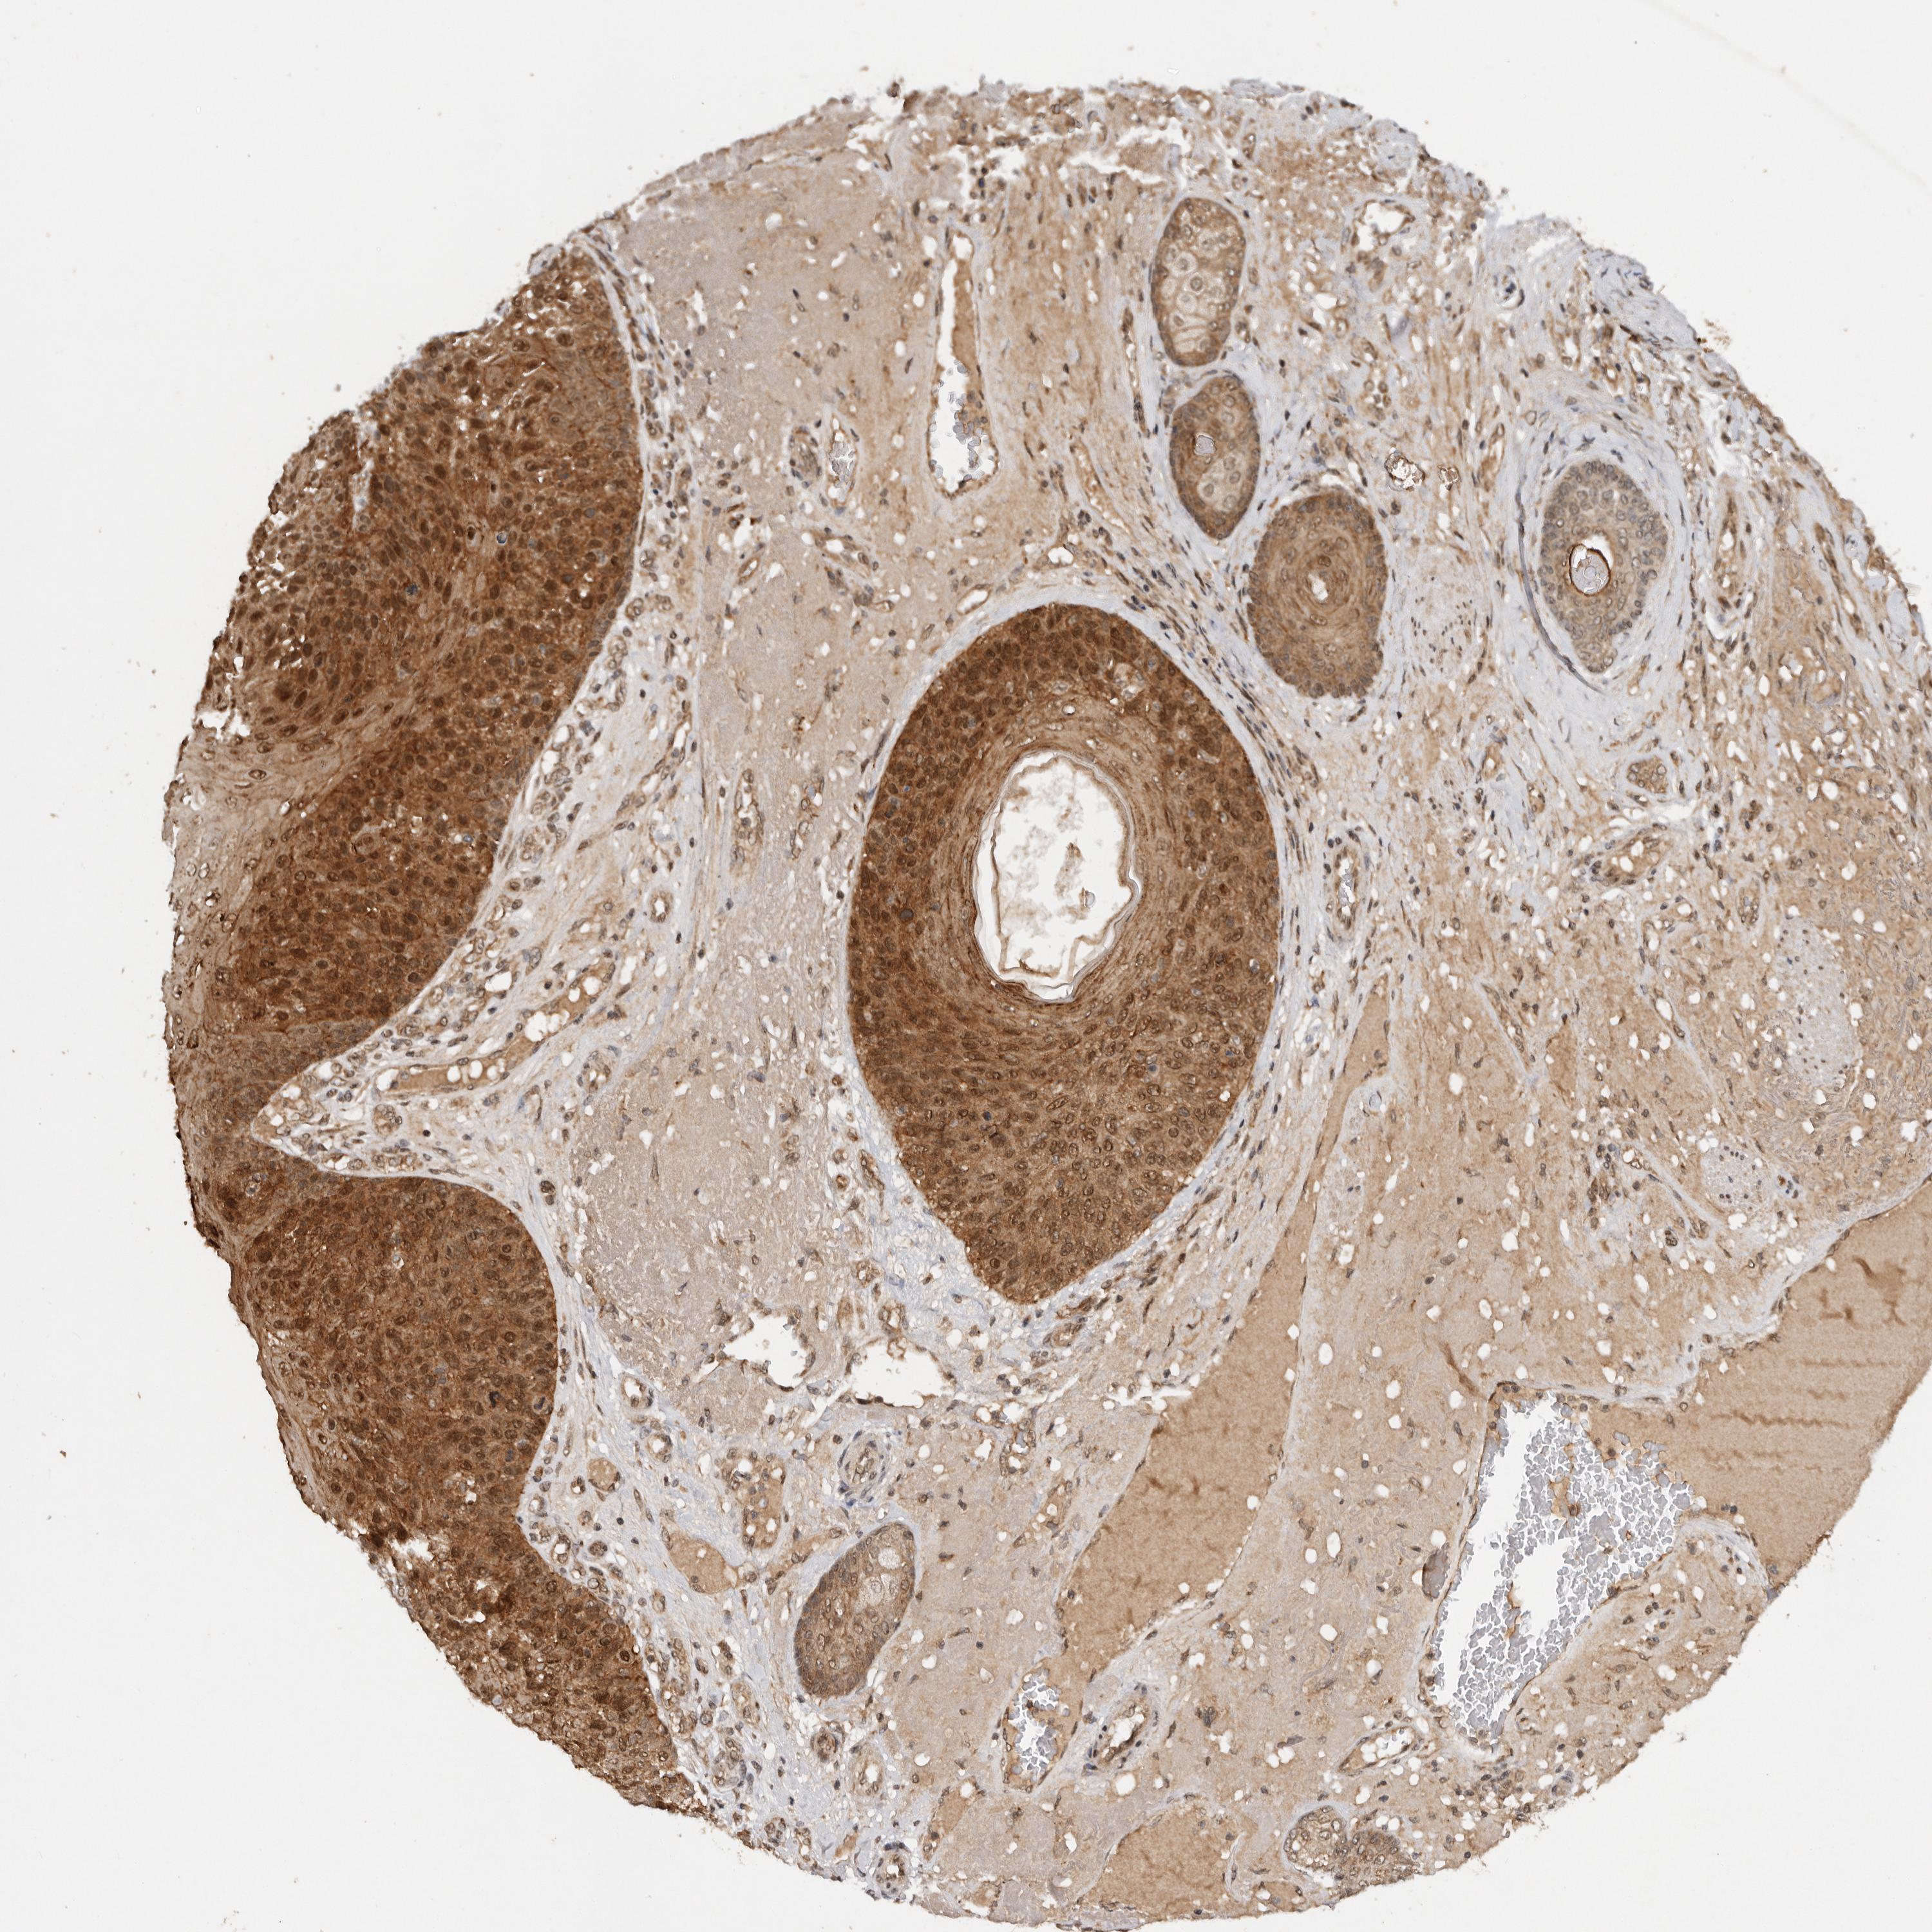

SKIN CANCER - Protein expressioni

A mouse-over function shows sample information and annotation data. Click on an image to view it in a full screen mode. Samples can be filtered based on level of antibody staining by selecting one or several of the following categories: high, medium, low and not detected. The assay and annotation is described here.

Antibody stainingi

Antibody staining in the annotated cell types in the current human tissue is reported as not detected, low, medium, or high, based on conventional immunohistochemistry profiling in selected tissues. This score is based on the combination of the staining intensity and fraction of stained cells.

Each image is clickable and will lead to virtual microscopy that enables deeper exploration of all samples and also displays staining intensity scores, fraction scores and subcellular localization as well as patient and tissue information for each sample.

Antibody HPA028626

Squamous cell carcinoma, metastatic, NOS

Squamous cell carcinoma, NOS